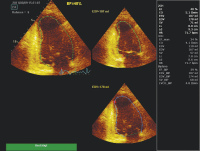

Echokardiographie aktuell: Basis- und erweiterte Evaluierung der systolischen Linksventrikelfunktion nach Myokardinfarkt

Journal für Kardiologie - Austrian Journal of Cardiology 2011; 18 (3-4): 102-104 Volltext (PDF) Abbildungen mit Filmsequenzen